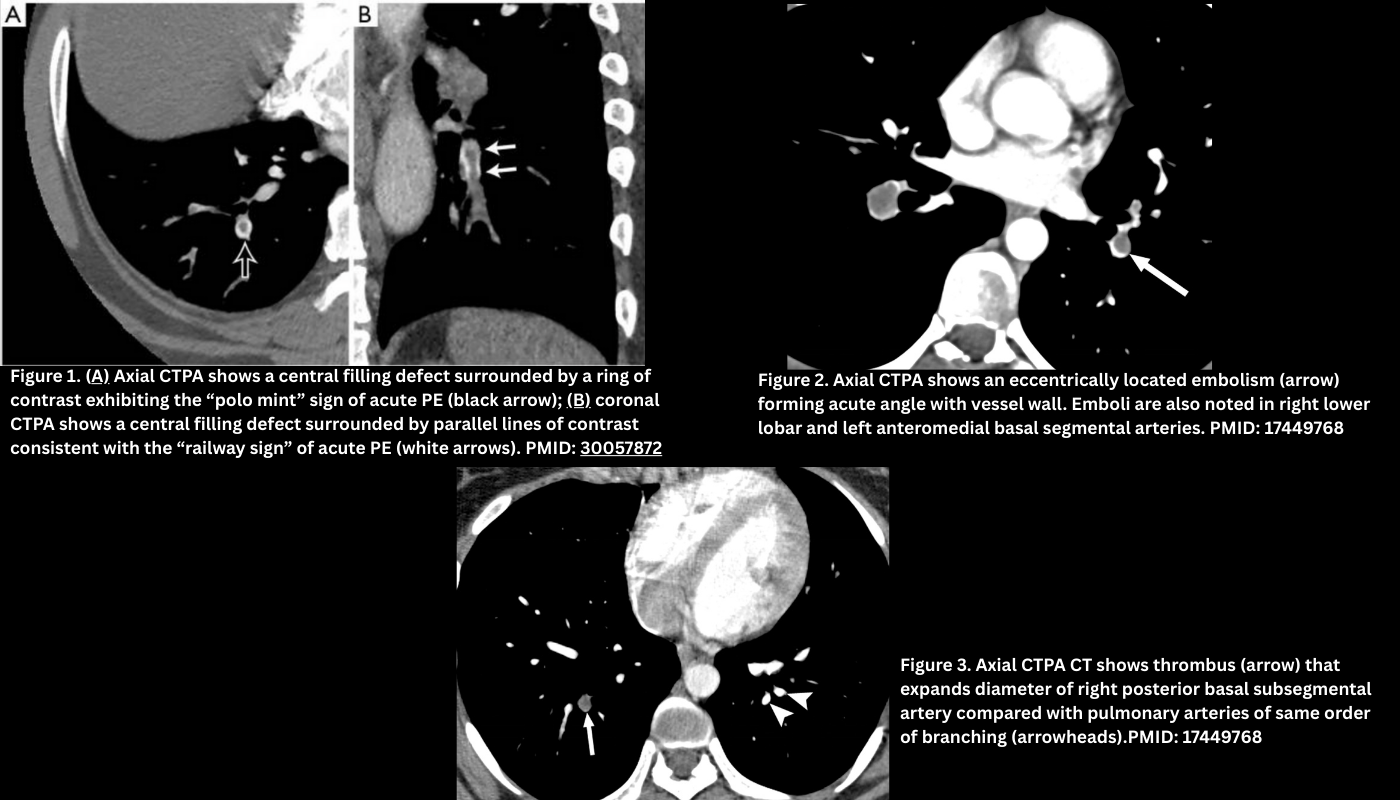

◾️Filling defect

- Appears as a low-attenuation area in a contrast-enhanced pulmonary artery.

- Should be visible in more than one plane and across several slices, with sharp borders to distinguish from flow artifact.

- Filling defects in acute PE may be non-occlusive (i.e., partially occlude the vessel) or occlusive (completely occlude the vessel).

- Non-occlusive filling defects. These filling defects can be located within the center of the involved vessel or, less commonly, adherent to the vessel (eccentric).

- Central. Most filling defects are central within the vessel lumen, surrounded by contrast, producing:

- Polo mint appearance: A central filling defect (the clot) surrounded by a rim of contrast within a circular cross-section of the pulmonary artery → looks like a polo mint in axial CTPA (Figure 1.A).

- Tram-track / railway sign: Endoluminal clot is surrounded by a rim of contrast on both sides (in coronal CTPA). Figure 1. B

- Eccentric (i.e., peripheral filling defects). Less commonly, in acute PE, the clot can be located in contact with the vessel wall. Typically, this clot forms an acute angle with the vessel wall (Figure 2).

- Note that in chronic thromboembolic disease, this angle is obtuse (see below for more information).

- Occlusive filling defects

- Occlusive PE prevents opacification of the entire lumen and may distend the vessel (Figure 3).

- Note that occlusive defects are nonspecific for acute PE and may occur in chronic thrombosis as well.

- Keep in mind that non-occlusive but flow-limiting PE can also reduce regional pulmonary blood volume.

B. Pulmonary Artery

The pulmonary artery containing an acute PE will be normal in size or expanded, compared to adjacent patent arteries, due to acute distension (Figure 3).